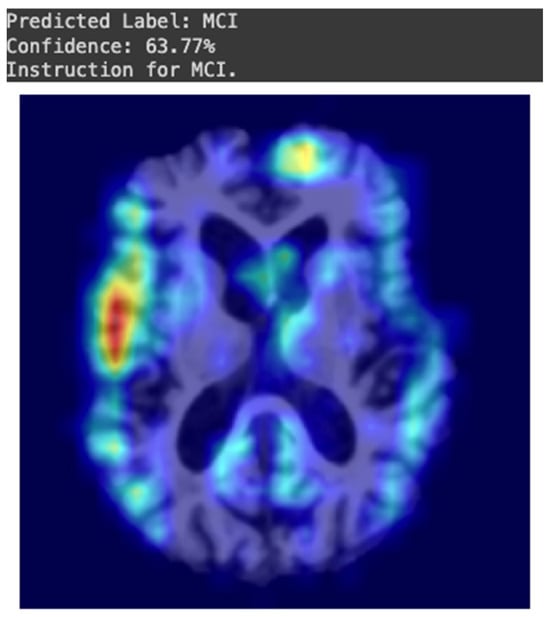

3.2. Proposed CDSS for Dementia Grad-CAM